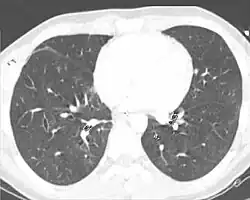

Tomografia computerizzata

La tomografia computerizzata (TC) è un esame decisamente più sensibile per la contusione polmonare,[1][51] ed è in grado di identificare lesioni addominali, toraciche, o di altro tipo che possono accompagnarsi alla contusione.[25] In uno studio scientifico è stato segnalato che la radiografia del torace rilevava una contusione polmonare nel 16,3% delle persone affette da un grave trauma toracico chiuso, mentre la tomografia computerizzata (TC) la rilevata in una percentuale decisamente più elevata e pari al 31,2% della medesima popolazione di traumatizzati.[62]

A differenza della radiografia del torace, la TC è in grado di rilevare la contusione polmonare quasi subito dopo l'infortunio.[9] Tuttavia, sia nel caso della radiografia sia della TC, la contusione polmonare diviene più evidente a distanza di 24-48 ore dal trauma, sotto forma di sanguinamento e comparsa di edema interstiziale polmonare.[63] La TC aiuta anche nella quantificazione di una precisa dimensione della contusione polmonare. Questo parametro è molto utile nel determinare se un paziente potrà aver bisogno di ventilazione meccanica. Una contusione che, sulla base del riscontro TC, interessa un ampio volume di polmone è associata a una maggiore probabilità di ventilazione artificiale. Secondo uno studio quando la contusione polmonare coinvolge circa il 30% del volume polmonare totale, pressoché tutti i pazienti necessitano di ventilazione meccanica.[64] La TC aiuta anche a differenziare tra contusione ed ematoma polmonare, difficilmente distinguibili basandosi sulla radiografia standard.[65] Tuttavia si deve anche tener presente che le contusioni polmonari visibili alla TC, ma non alla radiografia del torace, non sono di solito abbastanza gravi da influire sull'evoluzione del paziente o sul trattamento.[8]